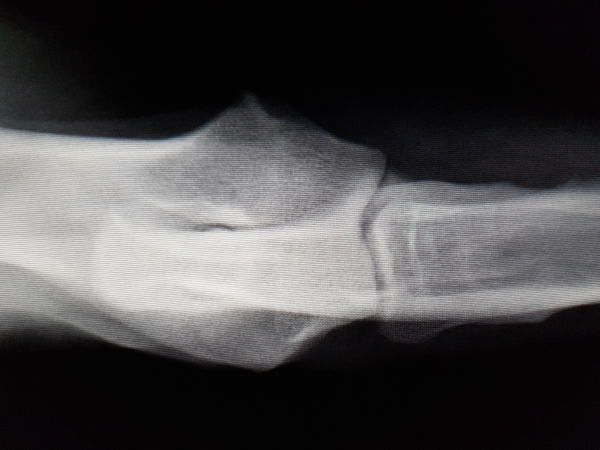

La Cirugía Traumatológica Veterinaria ha experimentado en estos últimos años una gran transformación y diríamos que casi una revolución, pues es de las especialidades que más rápidamente cambia tanto en sus técnicas específicas como en los materiales para llevarlas a cabo, lo que hace que ésta evolución hacia lo más correcto sea vertiginosa.